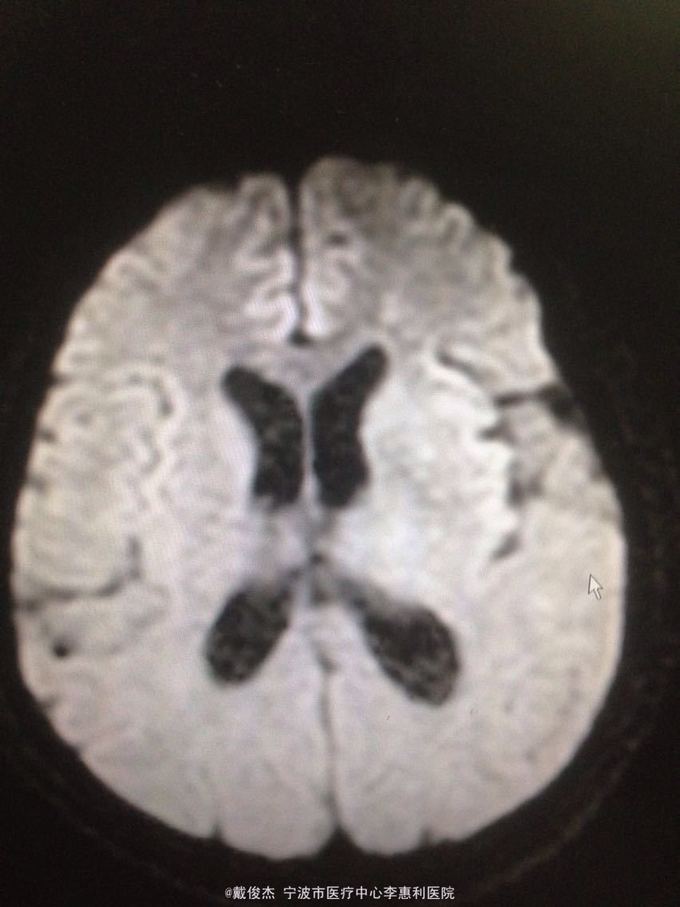

查体:神志清,双肺啰音,颅神经阴性,颈抵抗,四肢肌力正常,双巴氏征阴性 辅查:脑脊液压力380mmH2O,细胞4100/ul,多核90%,单核10%,蛋白223mg/ml。胸部CT示:两肺多发粟粒小结节。头颅MRI示:双侧大脑半球、脑干、小脑多发病灶。

诊断:结核性脑炎,肺结核 处理:抗痨治疗,激素,降颅压,保护神经和对症支持治疗